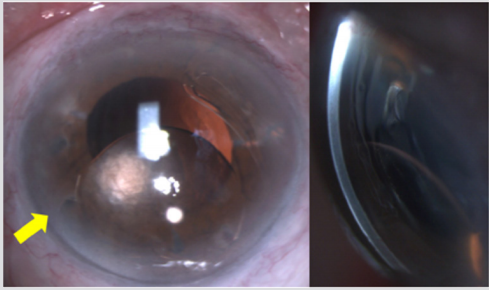

An 86-year-old otherwise healthy man presented due to visual deterioration of the right eye (OD) over the last 10 days. He reported undergoing phacoemulsification with implantation of an acIOL in the same eye 6 years ago while not recalling any ocular trauma in the recent past. He had also undergone phacoemulsification with posterior chamber IOL implantation in the left eye (OS) 5 years ago. At presentation, best-corrected visual acuity (BCVA) was 0.2 OD and 0.8 OS and intraocular pressure was 21 mmHg OD and 15 mmHg OS. Slit-lamp examination revealed a dislocation of the acIOL towards the inferior angle of the anterior chamber. Strikingly, the distal part of the inferior haptic appeared anterior to the decentered optic (Figure 1). The respective inferior haptic loop was not visible at its entire length as it was obscured by the corneoscleral limbus. Finally, a mild anterior chamber reaction was present while the cornea did not show any signs of edema. Central corneal thickness was 567μm OD and 566 μm OS and the corneal endothelial cell density was 1130 cells/mm2 OD and 1335 cells/mm2 OS measured with specular microscopy (Tomey EM-3000, Tokyo, Japan).

Figure 1: Slit-lamp photograph of the right eye depicting the inferiorly decentered acIOL (a) en face aspect and (b) lateral view. Please note the absence of significant corneal edema despite the contact between acIOL optic and corneal endothelium.